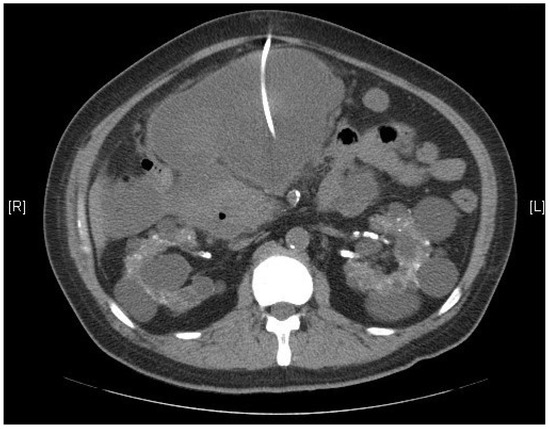

Giant Pancreatic Pseudocyst after Coronary Artery Bypass Graft in a Hemodialysis Patient: A Case Report

2. Case Report